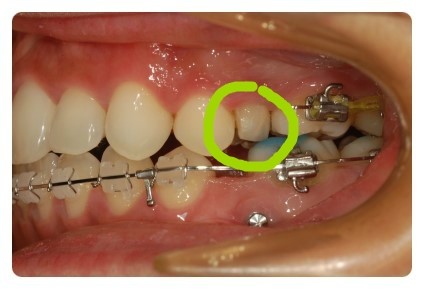

오늘따라 ~~~ 이뻐보이는 옆태 !!

저 동그라미 안에 있는것이 유치인데요 ~~~ 약해서그런지 많이 삭아있죠

사진 볼때마다 거슬렸는데 뽑고나니까 시원하네요 ㅋㅋ